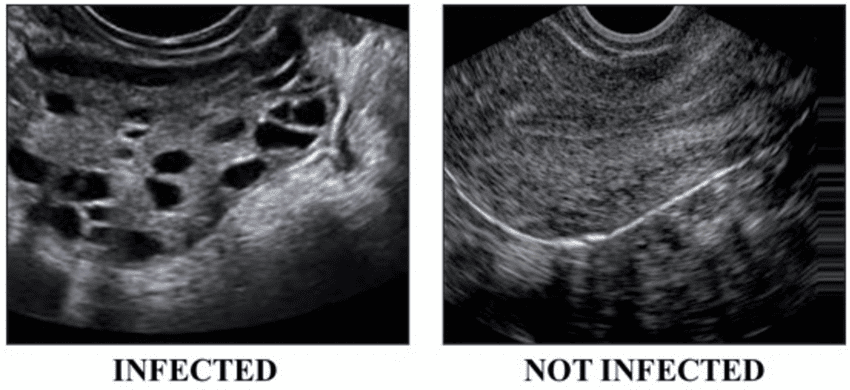

The term “polycystic” is often misunderstood. It does not mean you have large, painful cysts that need immediate removal.

In fact, the “cysts” are not true cysts but rather a large number of harmless, underdeveloped follicles (sacs containing eggs) that have stalled in their development due to the lack of proper ovulation.

On an ultrasound, these appear as small, pearl-like formations. It is critical to understand that not all women with PCOS will have polycystic ovaries visible on an ultrasound, and conversely, not all women with polycystic ovaries will have PCOS. Diagnosis requires meeting specific criteria beyond just this single finding.

This can be evident through clinical signs (hirsutism, acne, male-pattern baldness) or confirmed via blood tests. - Polycystic Ovaries on Ultrasound

Showing 12 or more small follicles (2–9 mm in diameter) in one or both ovaries, and/or an increased ovarian volume.

An imaging test to visually examine the ovaries. As mentioned, many cases show a characteristic “string of pearls” appearance—the hallmark of many small, underdeveloped follicles .